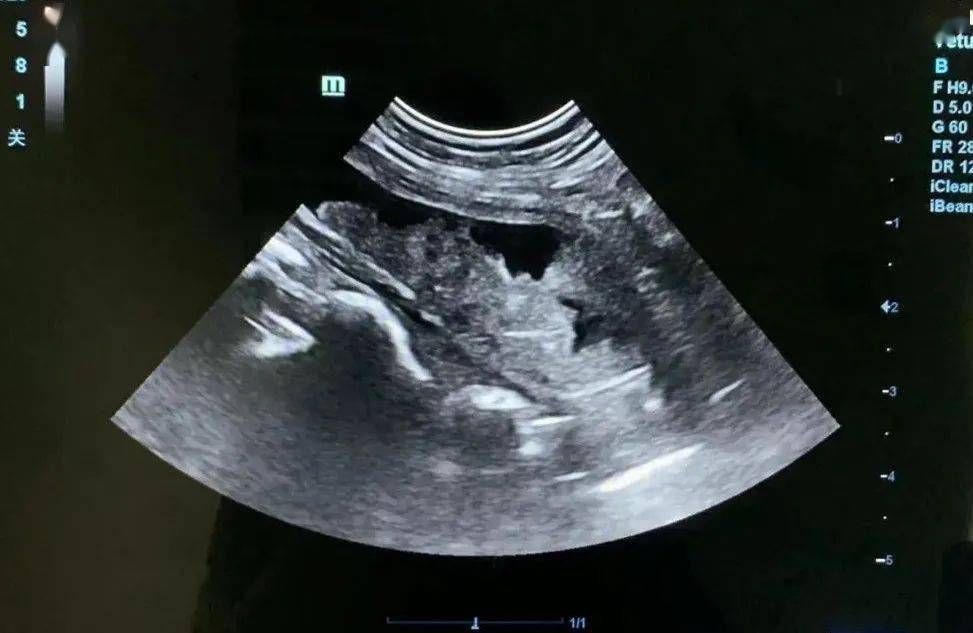

孕28周,胎儿腹部冠状切面,可见双侧肾脏下极融合位于脊柱前面膀胱上方

两个病例_胎儿_分析_解剖